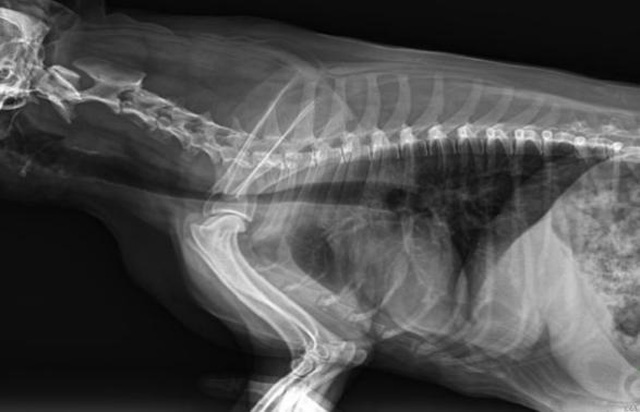

寵物DR是動(dòng)物專用的數(shù)字化攝影系統(tǒng),x線的穿透能力、低的輻射劑量,輻射劑量比X光低:熒光作用和感光作用,可以穿透動(dòng)物身體的結(jié)構(gòu)顯示成像,動(dòng)物的各個(gè)部位成像輔助獸醫(yī)診療。寵物DR采集時(shí)間10ms以下,成像時(shí)間僅為3秒,從檢查到出診斷報(bào)告大約5—10分鐘。較高的空間分辨力和低噪聲率,可獲得高清晰圖像。 DR成像數(shù)字化處理的特點(diǎn)可進(jìn)行后處理。提高了病灶的檢出率,這樣大大提高檢查的準(zhǔn)確率提高診斷準(zhǔn)確率避免漏診誤診等情況。